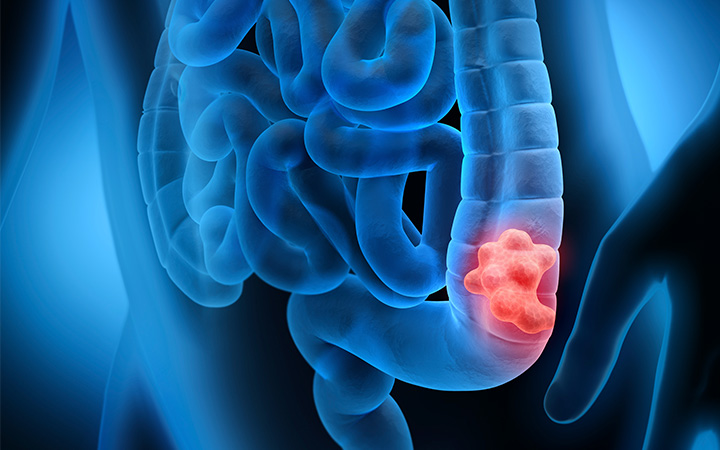

Ο καρκίνος του παχέος εντέρου συνδέεται με τις διατροφικές συνήθειες. Δίαιτα πλούσια σε ζωικά λίπη και πρωτεΐνες, κατεργασμένο κρέας με παραγωγή νιτροζαμινών κατά την πέψη, φτωχή σε φυτικές ίνες μπορεί να λειτουργήσει ως επαγωγός στην ανάπτυξη του καρκίνου του παχέος εντέρου. Ένας ασθενής με θετικό οικογενειακό ιστορικό σε αυτόν τον καρκίνο και μάλιστα σε ηλικία κάτω των 55 χρονών, θεωρείται ως πιθανός υποψήφιος για να παρουσιάσει καρκίνο στο παχύ έντερο. Επίσης άτομα που υποφέρουν από γενετικού τύπου ασθένειες του εντέρου (FAP, Crocknite Kanada, Gardner κ.α.) ή πάσχουν από ΙΦΝΕ (Crohn, ελκώδης, αμοιβαδική, φυματιώδης κολίτιδα) ή έχουν πολύποδες στο έντερο, φέρουν γεννεσιουργές αιτίες αυτού του καρκίνου.

Συμπτώματα του καρκίνου στο παχύ έντερο

Αίμα στα κόπρανα

Αλλαγή στις συνήθειες του εντέρου Τεινεσμός (Αίσθημα ατελούς αφόδευσης) Απώλεια βάρους

Απώλεια όρεξης

Αποφρακτικός ειλεός

Αναιμία.

Ανεξήγητος πόνος